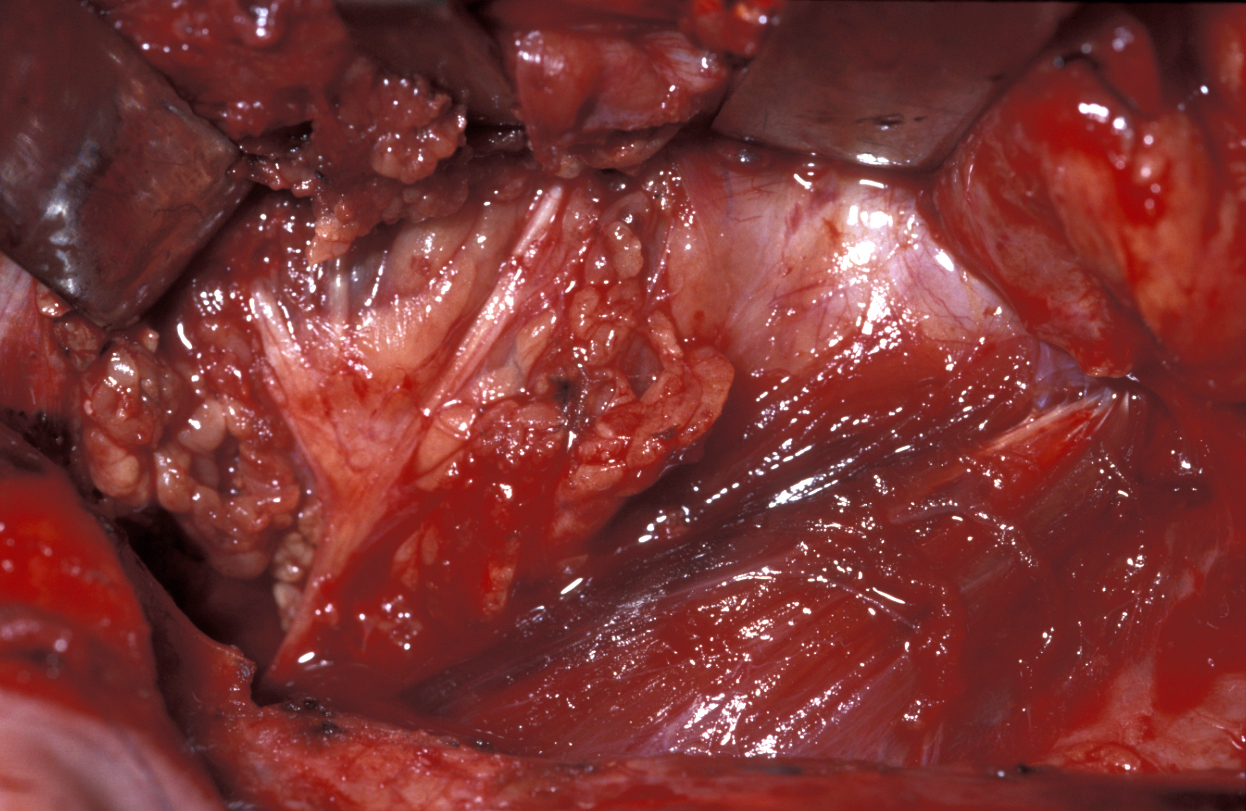

Submandibular gland excision is required after the gland has suffered irreparable damage from infection and/or obstructive disease. The surgical approach is by trans-cervical (from the neck) approach. The incision is two finger-breadths below the lower border of the mandible. A 3 to 4 cm incision is made. The incision is then deepened through fat that bleeds; bleeding needs to be controlled using bipolar diathermy to expose the platysma muscle (a broad sheet of muscle covering front and sides of the neck; see Figure 5).

Figure 5: Submandibular gland excision. The incision is two finger-breadths below the lower border of the mandible. After skin incision, control of bleeding and sweeping aside fat, the platysma muscle is exposed.

Platysma is divided and the lower border of the submandibular gland identified, enveloped in the submandibular fascia. The fascia is incised and an upper flap developed. The flap includes submandibular fascia, platysma, fat and skin. This approach and adhering to the gland will preserve the function of the marginal mandibular branch of the facial nerve. The superficial pole of the gland is mobilised posteriorly (on the back; see Figure 6), if need be by ligating the facial vessels (but this is not always needed), anteriorly by counter-traction and inferiorly by finger dissection.

Figure 6: The submandibular gland lies immediately underneath platysma enveloped in fascia. Sticking to the glandular surface (in glands without tumour) is a safe way to protect the marginal mandibular branch of the facial nerve.